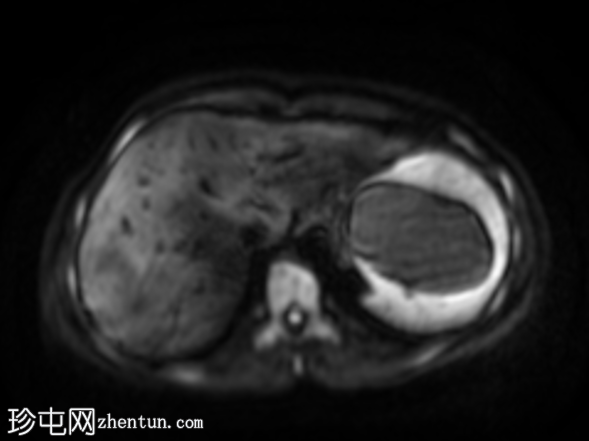

轴位

STIR序列

肝脏肿大,可见多发性双叶肝囊肿。

脾脏肿大,可见多发性大囊肿,内层脱离。

肝脾包虫囊肿的典型

影像

学表现。